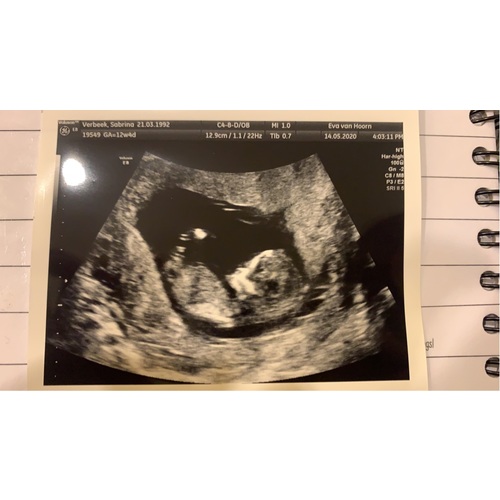

Hier precies 12 weken. Wie kan mij helpen? 馃槉

Ik neig naar jongen. Had je nog een andere foto ter vergelijking?

6 jaar geleden

Nee helaas :( maar een foto gekregen